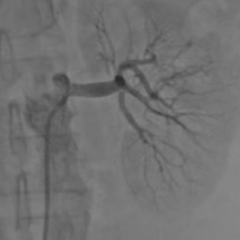

“正常肾动脉像小指般粗,而患者的左肾动脉只剩一丝缝隙。”龙双祁主任指着CT血管成像结果解释,“95%的狭窄程度意味着左肾已处于‘饿死’边缘,这也是患者血压飙升到220毫米汞柱的根源所在。”面对如此危重的病情,龙双祁立即组织科室骨干进行多学科会诊,心血管介入专家团队及护理团队共同参与,制定了周密的手术方案。

手术采用最新的微创介入技术,仅通过患者大腿根部一个针眼大小的切口进行操作。随着手术团队一系列精准操作,一枚金属支架被稳妥放置在左肾动脉狭窄处。当最后的球囊撤出时,显示屏上原本纤细如丝的血流瞬间变得充盈——左肾动脉恢复通畅,肾脏重新获得充足血流。监测仪显示,患者原本高达180/110毫米汞柱的血压在手术过程中已稳步下降至150/90毫米汞柱左右。